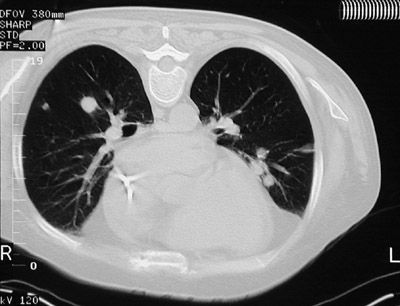

| There are scattered circumscribed nodules involving the lung parencyma in a patient who received an organ transplant. The nodules are seen above with high resolution chest CT scan and below with lung window (and the patient prone). A biopsy showed these lesions to be foci of post-transplantation lymphoproliferative disorder (PTLD). Immunosuppressive therapy creates an environment in which a lymphoid proliferation occurs that can resemble a lymphoma. The lesions often decrease or disappear if immunosuppression is diminished. |